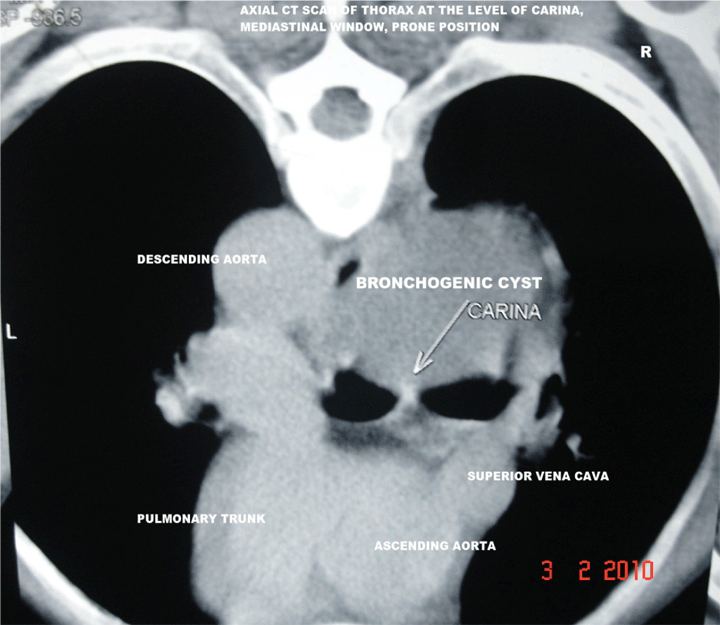

A 35-year-old male patient was presented with sense of heaviness in chest and shortness of breath even at rest for past two years. He gave history of intermittent low grade fever, cough, right sided pain chest since his adolescence and was frequently treated with antibiotics. Chest X-ray showed a right sided mediastinal mass with ipsilateral peripheral pleural calcification in the mid/lower zone. Electrogram and echocardiography were within normal limits. The CT scan of thorax showed a right sided posterior mediastinal, unilocular, cystic mass lesion having diameter of 10.9x8 cm with a homogeneous, increased fluid attenuation value of +15 HU. (Figure 1) On contrast study the cyst was thin-walled, nonenhancing except a small part of its right edge suggesting focal thickening of inflamed mediastinal pleura or compressed part of lung adjacent to the cyst. (Figure 2) A fluid was found at its dependent part, both in supine and in prone position due to presence of a small amount of higher density fluid. (Figure 1) (Figure 2) and (Figure 3) A focus of calcification was found in a part its periphery. (Figure 3) Absence of air within the cyst proved that the cyst was noncommunicating. Right intermediate bronchus was partially compressed and slightly displaced by the mass. (Figure 4) Associated ipsilateral periopheral pleural calcification was present. The CT guided aspiration revealed its content to be whitish, opalescent fluid with high protein, epithelial cells, amorphous calcium. Culture report was negative. Fibreoptic bronchoscopy revealed mucosal thickening and mild narrowing of lumen of right intermediate bronchus due to extrinsic compression. Bronchoscopic biopsy specimen revealed inflammatory changes and no malignant cell was detected.

Figure 4: Axial computed tomography scan of thorax at the level of carina; mediastinal window, prone position.